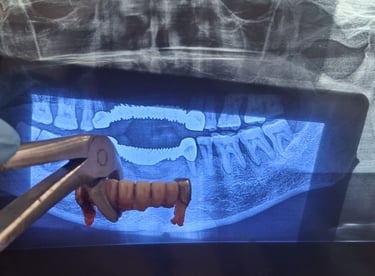

Teeth Extraction

All images shown here represent real clinical cases of teeth extractions done at our dental clinic with patient consent.

Tooth extraction is performed when a tooth is severely damaged, infected, or cannot be saved through other dental treatments. At Shree Dental Care, we carry out tooth extractions using gentle techniques to ensure minimal discomfort and faster healing.

Patients from Shyamal and nearby areas of Ahmedabad visit our clinic for comfortable teeth extractions carried out using modern techniques and strict hygiene protocols.

At Shree Dental Care, we ensure:

Thorough clinical examination and digital X-rays.

Gentle and painless extraction techniques.

Proper anesthesia for patient comfort.

Post-extraction care instructions for fast healing.

Our goal is to make the procedure as smooth and stress-free as possible.